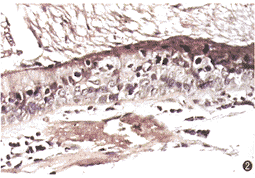

細胞的重要性

細胞學是研究細胞結構和功能的生物學分支學科。

細胞是組成有機體的形態和功能的基本單位,自身又是由許多部分構成的。所以關於細胞結構的研究不僅要知道它是由哪些部分構成的,而且要進一步搞清每個部分的組成。相應地,關於功能不僅要知道細胞作為一個整體的功能,而且要了解各個部分在功能上的相互關係。